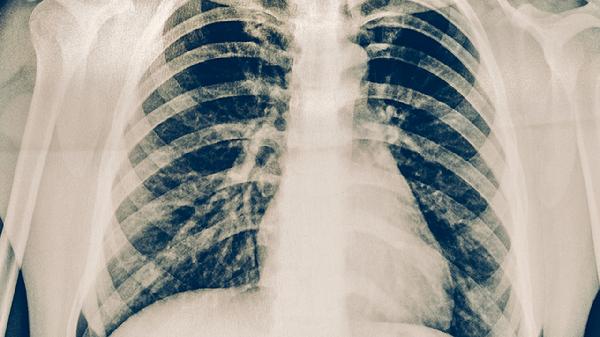

肺結(jié)核主要由結(jié)核分枝桿菌感染引起,傳播途徑包括飛沫傳播、密切接觸傳播、消化道傳播等。導(dǎo)致肺結(jié)核的高危因素主要有免疫力低下、長(zhǎng)期吸煙、糖尿病控制不佳、居住環(huán)境擁擠、職業(yè)暴露等。肺結(jié)核患者可能出現(xiàn)咳嗽、咳痰、咯血、低熱、盜汗、乏力等癥狀,建議及時(shí)就醫(yī)治療。

血糖控制不佳的糖尿病患者肺結(jié)核發(fā)病率顯著增高。高血糖環(huán)境有利于結(jié)核分枝桿菌生長(zhǎng)繁殖,糖尿病患者細(xì)胞免疫功能受損也增加了感染風(fēng)險(xiǎn)。糖尿病患者需要嚴(yán)格控制血糖,定期進(jìn)行胸部X線檢查。合并肺結(jié)核的糖尿病患者需要在治療結(jié)核的同時(shí)加強(qiáng)血糖監(jiān)測(cè),可使用胰島素控制血糖。